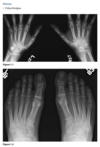

Anteroposterior view of the hands of a

patient with chronic renal failure shows subperi-

osteal resorption along the radial aspect of the

middle phalanges of the index and middle fingers

(Fig. 2.23.1, arrows). There are vascular clips from

a graft at the radial aspect of the right wrist (arrow-

heads). A lateral view of the skull in the same patient

(Fig. 2.23.2) shows a salt-and-pepper appearance.

Secondary hyperparathyroidism (HPT)

HPT is a general term referring to an

increased serum level of parathyroid hormone. Pri-

mary HPT results from an intrinsic abnormality in

the parathyroid gland (e.g., an adenoma, hyperpla-

sia, carcinoma). Secondary HPT is caused by a dif-

fuse, adenomatous hyperplasia, and tertiary HPT

develops from an autonomous parathyroid ade-

noma caused by the chronic overstimulation of hy-

perplastic glands in renal insufficiency.

Bone resorption along the radial aspect of

the middle phalanges of the hand (especially of the

second and third digits) is considered diagnostic of

this disorder.

Bone softening may lead to

basilar invagination, wedged vertebrae, bowing of long bones, and slipped capital femoral epiphyses.

Brown tumors, which are lytic, expansile lesions

that may mimic metastases or myeloma, occur in

the jaw, rib, and pelvis and are more commonly

seen in primary HPT. Osteosclerosis, more com-

monly seen in secondary HPT, is characterized by

bandlike sclerosis on the superior and inferior sur-

faces of the vertebral body (i.e., rugger-jersey spine;

Fig. 2.23.4). Soft-­ tissue calcifications can occur in

the viscera, cornea, periarticular regions, and hya-

line or fibrocartilage, causing chondrocalcinosis